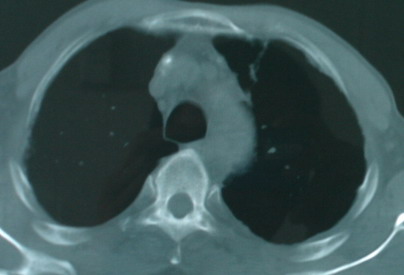

以下是引用卜一在2008-6-3 19:33:00的发言:[br]双肺结节,以双上肺分布为多,期间搀杂片状致密影及索条致密影。考虑:继发性肺结核伴血型播散可能性大。不除外肺泡ca的可能!另:椎体退变!

以下是引用panyishengct在2008-6-3 21:09:00的发言:[br]双上肺弥漫性小结节影,纵隔窗内钙化淋巴结影,考虑矽肺或/和tb可能性较大,不除外肺ca可能。腰椎考虑退变。 [br][br]